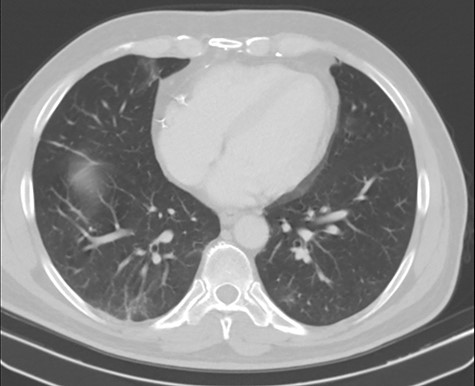

A 53-year-old man with a 10-day evolution of mild COVID-19 was admitted to the emergency department. He had a 2-day evolution, severe and sharp abdominal pain, which was located in the epigastrium, worsening in intensity on the last day. He also reported fever (38°C). The patient did not have nausea, vomit, abnormal bowel movements, other respiratory symptoms or urinary complaints. His medical history included arterial hypertension, dyslipidemia and a previous myocardial infarction submitted to coronary bypass surgery in 2013. A physical examination revealed a febrile (38.1°C) and stable patient (blood pressure (BP): 125/82 mmHg; hazard ratio (HR): 89 bpm). Cardiopulmonary auscultation was normal. His abdomen was non-distended, and tender mass in the epigastrium with localized guarding was noted. Bowel sounds were hypoactive and non-metallic. No abdominal hernias were identified. Laboratory exams revealed a normal white blood cell count (8.130/μl; segmented neutrophils, 72.9%), a hemoglobin level of 13.80 g/dl, a C-reactive protein level of 22.10 mg/dl, a d-dimer level of 0.94 μg/ml and normal hepatobiliopancreatic, cardiac and renal biochemical parameters. Urinalysis and the arterial-blood gas test were also normal. Ultrasonography was not performed due to its unavailability at the hospital on that day. A computed tomography (CT) scan with intravenous contrast of the abdomen was obtained, detecting a short segment of small bowel with inflammatory signs and localized free peritoneal fluid (Fig. 1). The pulmonary bases had residual ground-glass opacities related to COVID-19 (Fig. 2). Common diagnosis such as cholecystitis, pancreatitis or perforation of hollow viscus were ruled out. Given the lack of a preliminary diagnosis and the evidence of ongoing abdominal sepsis, the patient was proposed for a diagnostic and potentially therapeutic exploratory laparotomy. The intraoperative findings revealed a suppurative Meckel’s diverticulitis with local abscess, found at about 50 cm from the ileocecal valve (Fig. 3). Drainage and a segmental ileal resection with primary anastomosis were performed. In the postoperative period, inflammatory markers were responding positively to intravenous antibiotics and no further rises in temperature were observed. In addition, no complications were reported, and the patient was discharged on postoperative Day 6. The anatomopathological examination revealed small bowel with active inflammation and gangrenous Meckel’s diverticulum.